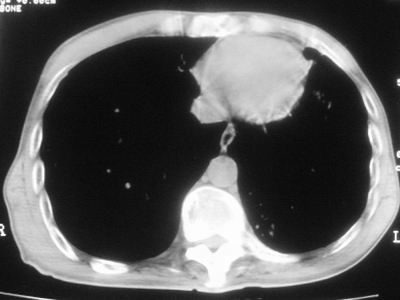

标题: CT11864:男,47岁,反复咳嗽、咯痰、咯血3年,请分析. [打印本页]

患者,男,47岁,反复咳嗽、咯痰、咯血3年,再发5天。痰培养未找到真菌、抗酸杆菌、癌细胞。

左肺上叶体积明显缩小,其内见多发透光区,纵隔向左侧移位,左肺下叶多发班片状病灶,边界模糊,1左肺上叶先天肺发育不全,2左肺下叶肺炎,

左肺上叶结核伴肺纤维化,纵隔移位,左肺下叶感染性病变,建议抗炎抗结核后复查,双肺气肿.

以下是引用xulianj在2008-2-25 21:01:00的发言:[br]左肺上叶结核伴肺纤维化有霉菌球形成,纵隔移位,左肺下叶感染性病变,建议抗炎抗结核后复查,双肺气肿.

考虑:左肺慢纤伴霉菌球形成、双肺全小叶型肺气肿。

1)考虑为:左肺上叶肺结核(空洞形成),伴左下肺感染;不排除霉菌感染可能。2)肺气肿。

左肺上叶结核伴肺纤维化空洞形成并左肺下叶感染,纵隔牵拉移位,建议作进一步检查排除左侧肺霉菌感染可能。